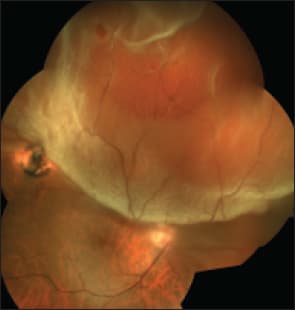

High cutting rates and higher fluidic resistance at the port are beneficial for all cases and all tasks because they decrease pulsatile vitreoretinal traction on both detached and attached retina and reduce the risk of iatrogenic retinal breaks (Figure). I refer to the amount of fluid that passes through the port during an open-close cycle as “pulse flow.” High cutting rates produce low pulse flow with many small-volume pulses and with fewer remote effects — in other words, less pulsatile vitreoretinal traction.

Figure. High cutting rates are beneficial because they reduce iatrogenic retinal breaks.